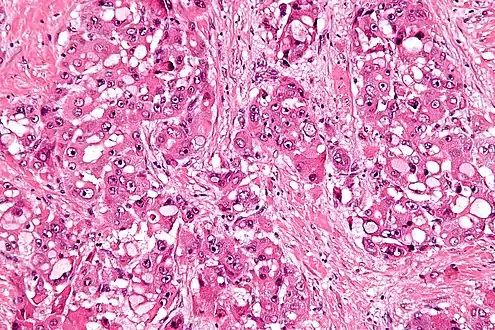

| Micrograph of fibrolamellar hepatocarcinoma showing the characteristic laminated fibrosis between the tumor cells with a low NC ratio. H&E stain. | |

The histopathology of FLC is characterized by laminated fibrous layers, interspersed between the tumor cells. Cytologically, the tumor cells have a low nuclear to cytoplasmic ratio with abundant eosinophilic cytoplasm.[1] Tumors are non-encapsulated, but well circumscribed, when compared to conventional HCC (which typically has an invasive border).

Intermed. mag. High mag.

High mag.